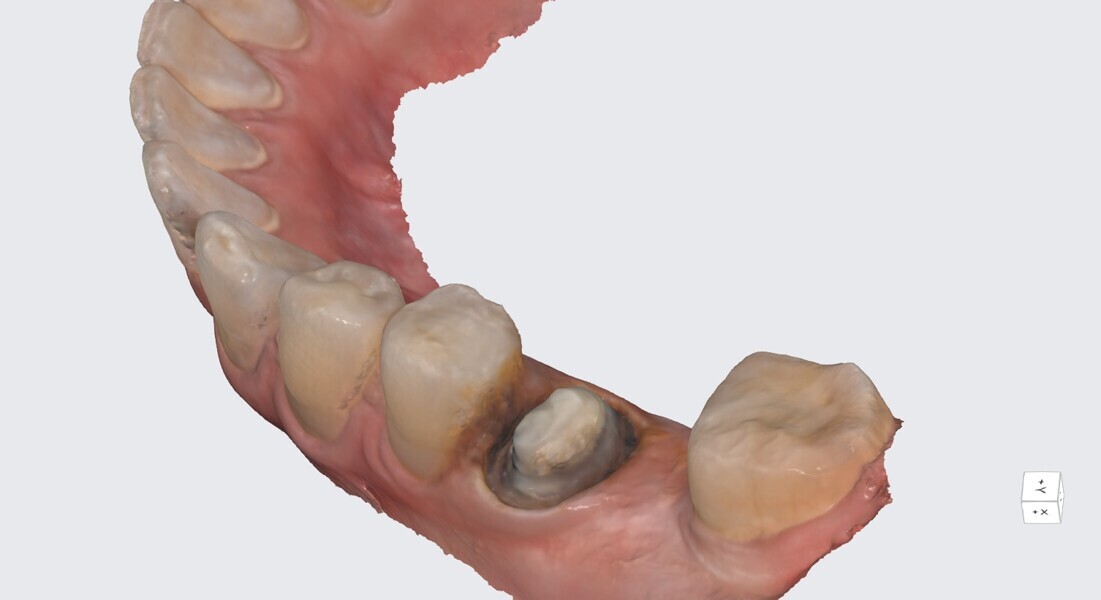

One year later, the restoration was performing well and the patient was asymptomatic. Radiographs and a CBCT control scan showed complete bone healing. On the periapical radiograph, the tooth showed a healthy periodontal ligament and no signs of failure in the restoration (Fig. 12). The cross-sectional, axial and coronal views of the CBCT scan showed good bone width and height and no pathological findings (Figs. 13–16). The oclusal scans and clinical images showed good adaptation of the new restoration and a healthy gingiva (Figs. 17–20).